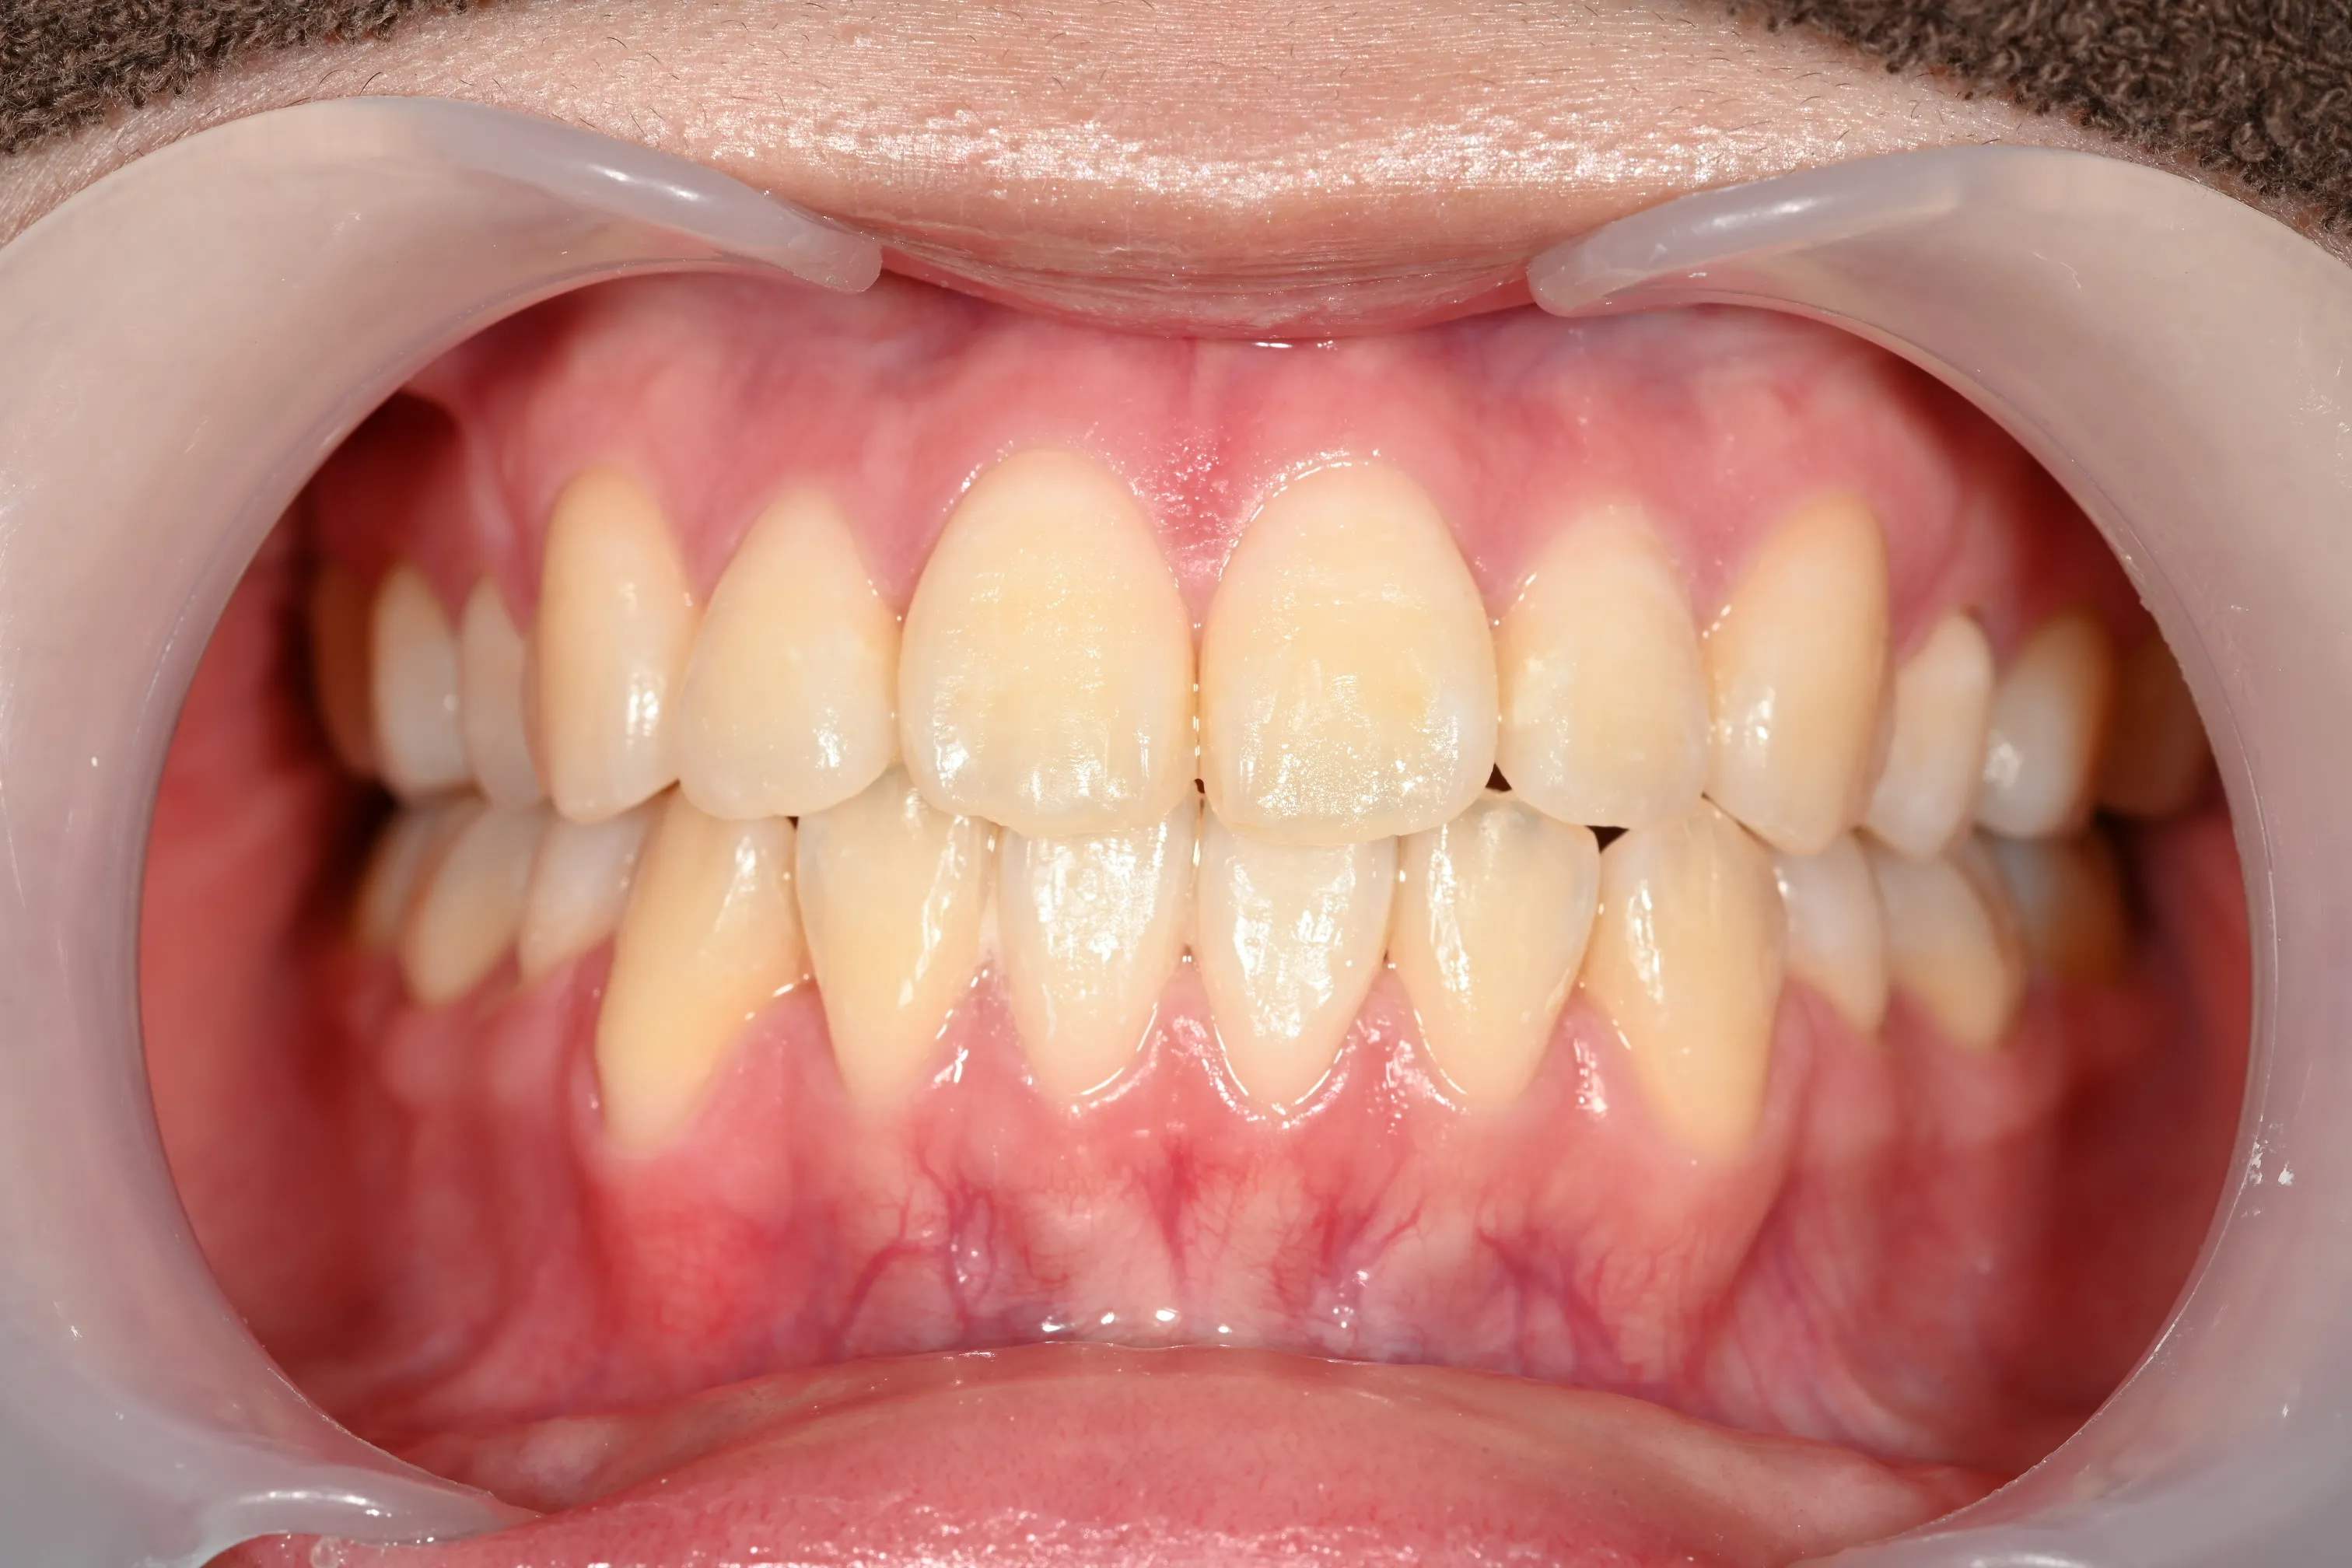

症例2_治療前 症例2_治療後

年齢・性別 31才・男性

治療方法 ブラケット矯正

治療期間 3年

治療総額 850,000円

特記事項 抜歯あり(4本抜歯)